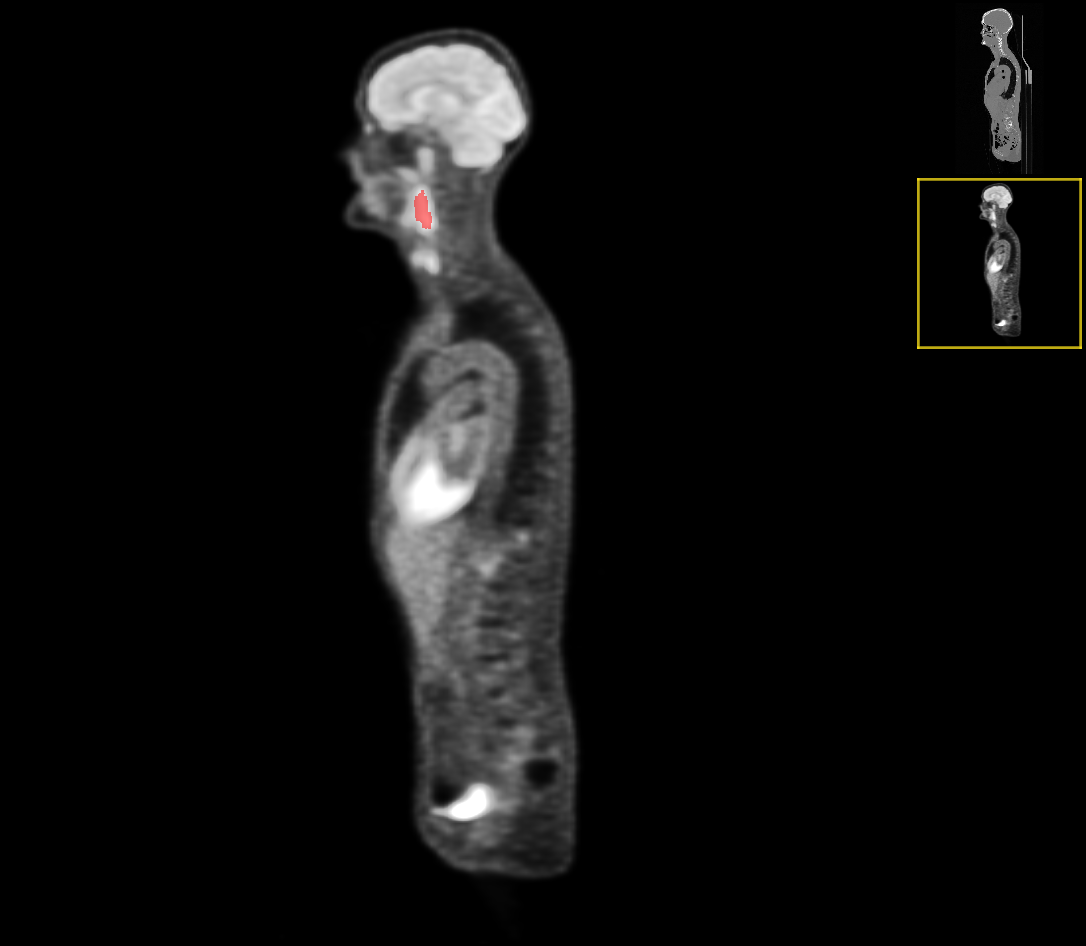

The ground truth labels usually include a single mass of the primary tumor (but in some cases it was absent completely or had two components), and several connected components of the annotated lymph nodes. An example case of CT and the corresponding PET image with ground-truth overlays is shown in Figures 1 and 2.